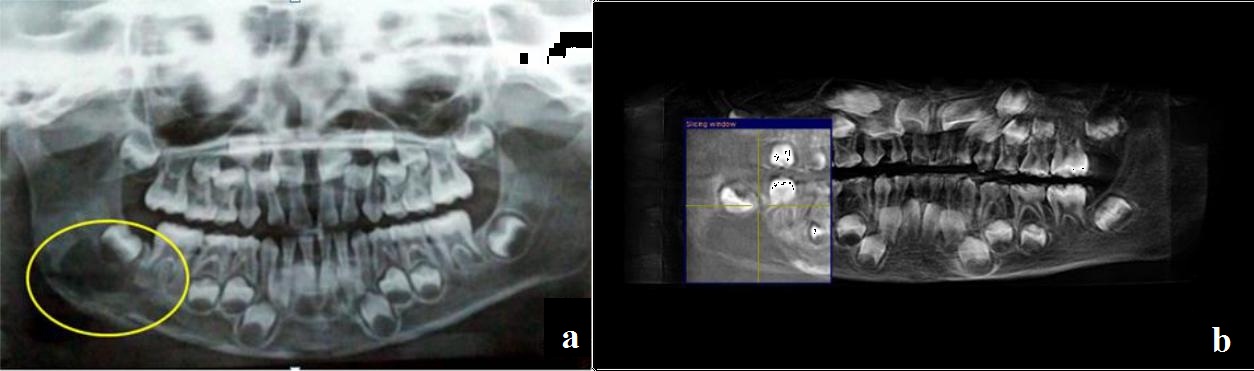

A five-year-old child patient came with a chief complaint of intermittent pain on the lower right side of the face since one month duration. Swelling was small in size and gradually increased to present size. On extra-oral examination, a localized swelling measuring approximately 4x5cm extending anteriorly from the right commissure of the lip up to the angle of mandible. Inferiorly up to the lower border of the mandible [Table/Fig-1]. Lymph node examination revealed two palpable submandibular lymph nodes on the right side which were mobile and tender on palpation. Intra-oral examination presented with restricted mouth opening with inter-incisal opening of 1.5cm and an ovoid solitary swelling in relation to the right buccal sulcus in relation to 43 to an erupting 47 extending till the retro-molar trigone which was tender on palpation [Table/Fig-2]. On bimanual palpation, expansion of the buccal and lingual plate was present. Orthopantomogram (OPG) and Cone Beam Computerized Tomogram (CBCT) revealed an ill-defined radiolucency from the mesial root of 46 to the ascending ramus with expansion of the lower border of the mandible [Table/Fig-3]. To diagnose the involvement of other systems in this triad a diagnostic 99 TC-MDP whole body scintigraphy was performed. The scintigraphy showed an increase tracer pooling in the right side of the mandible with no evidence of bony metastasis at other sites of the body [Table/Fig-4]. An incisional biopsy was deferred as the patient was uncooperative to local anaesthetic procedure. Patient was taken up for localized lesion enucleation, bone curettage and extraction of the tooth germ (46 and 47) with excision of the right submandibular lymph node. Under general anaesthesia, right Risdon’s submandibular incision was placed and layer by layer dissection was performed to reach the submandibular region [Table/Fig-5]. The submandibular lymph node was removed. Facial artery was ligated and the lower border of the mandible was reached. The lesion was identified and enucleated. Peripheral ostectomy was done for the adjacent bone along with removal of 47 tooth follicle [Table/Fig-6]. Haemostasis was obtained. The curetted specimen was sent for histopathological analysis which was suggestive of solitary eosinophilic granuloma [Table/Fig-7a]. For confirmatory diagnosis, an immunohistochemistry was performed which showed CD 1A immunoreactive in the tumour cells correlating with Langerhans Cell Histiocytosis (LCH) [Table/Fig-7b]. Post-operatively, patient was treated with the Tablet Indomethacin 300 mg BD regimen for a period of 2 months. Radiotherapy was deferred due refusal of the parents. He was periodically observed for a year and showed no evidence of recurrence till date. A one year post-operative OPG showed good wound healing with no signs of recurrence of the lesion [Table/Fig-8].

(a) Orthopantomogram; (b) Cone beam CT – showing the lesion on the right side mandible.